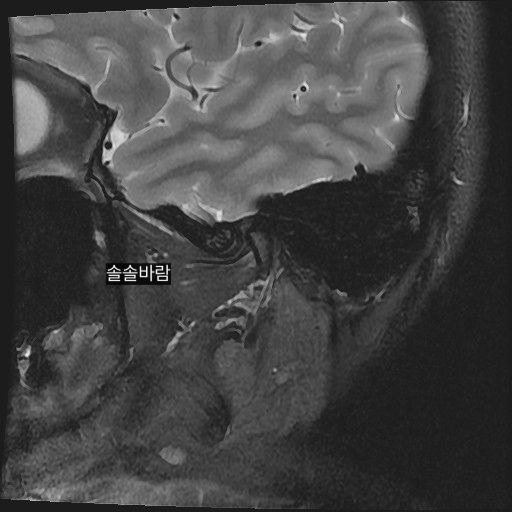

구강내과 턱 MRI 어느 사진이 우측? 좌측?인지 어떻게 보나요? 디스크 두꺼워짐 심한가요?ㅜ

구강내과 턱 MRI 사진 보는데 귀 위치가 다 똑같아서요

어느 사진이 우측? 좌측?인지 어떻게 보나요?

그리고 사진 상 디스크 두꺼워짐 심한가요?ㅜ

현재 사진만으로는 정확히 왼쪽이나 오른쪽이다 라고 할 수 없습니다. 이는 데이터 상의 reference가 필요하며 보통은 해당 부위가 질문자님 기준으로 좌측일 가능성이 가장 크나 이는 좌우 반전을 할 수 있기 때문에 무조건 좌측이라고 할 수 없습니다. 현재 개구시와 폐구시에 보았을 때 condyle (아래턱 부위의 일부)가 disc를 넘어가지 못하고 있으며 이러한 경우 개구제한이 있거나 넘어가더라도 소리가 나면서 넘어갈 수 있습니다. 일부 염증도 보이고 있으므로 내과적인 치료를 하셔야 할 것으로 보입니다.

사실 일반치과의사는 턱관절 MRI를 판독하기 쉽지 않습니다. 일반적으로 구강내과전문의정도는 되야 판독가능하며, 왼쪽 오른쪽을 구분하는건 MRI에 표시되며, 정확한건 구강내과 전문의에게 소견을 듣는게 가장좋습니다.